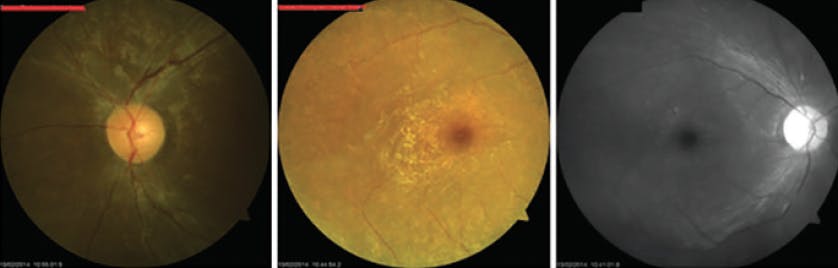

At 8 years, a fundoscopic examination revealed pallor of the patient’s optic disc, vascular attenuation, and a diffuse grainy appearance of the retinal pigment in the periphery in both eyes (Figure 1). Electroretinography (ERG) revealed bilateral low amplitude for waves A, B, and C under scotopic conditions, suggestive of severe pigmentary retinopathy.

<p>Figure 1. Fundoscopy at presentation showed pallor of the optic disc, vascular attenuation, and a diffuse grainy appearance of pigment in the retinal periphery.</p>

Figure 1. Fundoscopy at presentation showed pallor of the optic disc, vascular attenuation, and a diffuse grainy appearance of pigment in the retinal periphery.

Follow-up fundus examination revealed circular bands of shades of pink and orange in the retina resembling bull’s eye maculopathy, mild bone spicule pigmentation in the retinal periphery, and nerve fiber layer atrophy (Figure 3). Genetic testing revealed a mutation on the CLN3 gene with the variant Arg334His, consistent with JNCL.

<p>Figure 3. Follow-up fundoscopy after 4 years revealed circular bands of shades of pink and orange in the retina (resembling bull’s eye maculopathy), mild bone spicule pigmentation in the retinal periphery, and nerve fiber layer atrophy.</p>

Figure 3. Follow-up fundoscopy after 4 years revealed circular bands of shades of pink and orange in the retina (resembling bull’s eye maculopathy), mild bone spicule pigmentation in the retinal periphery, and nerve fiber layer atrophy.

Our patient’s fundus findings included all of the classical JNCL retinal signs: early macular alteration (ie, a bull’s eye pattern with a brownish color of the macula), narrowing of the vessels, peripheral bone spicules, and a pale optic disc.2-5